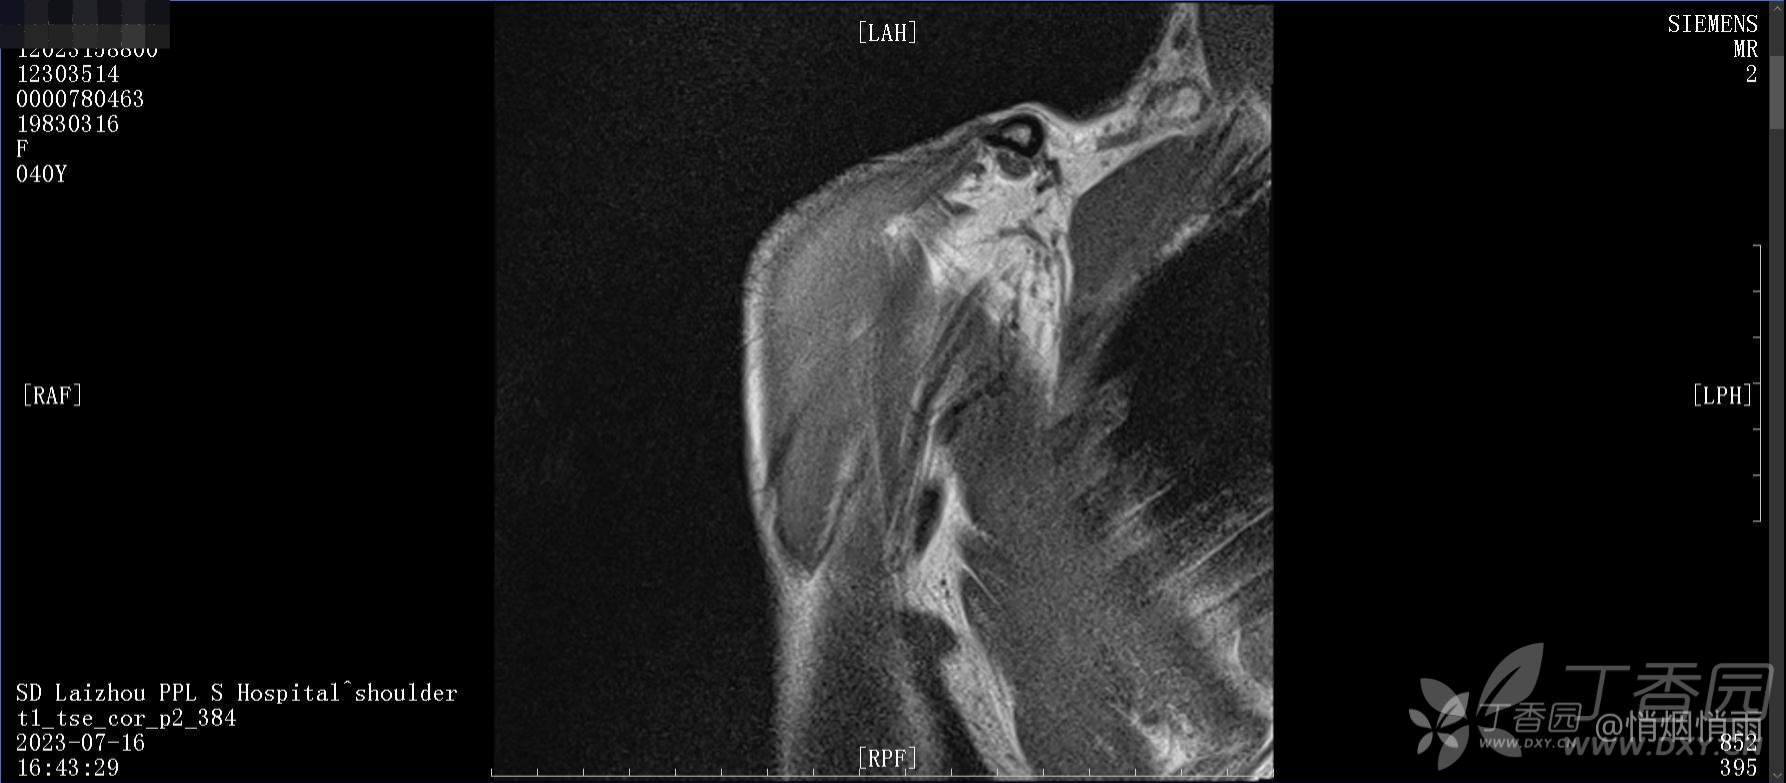

查体:右肩关节局部轻度肿胀,肩胛区压痛明显,痛处不固定,肩关节痛性活动受限,jobe test(+),lift -off test(+),中指、环指感觉较余指减退,余肢端感觉及血运情况可。

目前的诊断,暂时依据辅助检查诊为肩袖损伤,但是患者疼痛的性质和特点,却不是单纯的肩袖损伤所致。考虑过胸廓出口综合征,但是该疾病会出现肩胛区的疼痛吗?(由于考虑到费用的问题,没再进行下一步的检查)带状疱疹会有如此的症状吗?